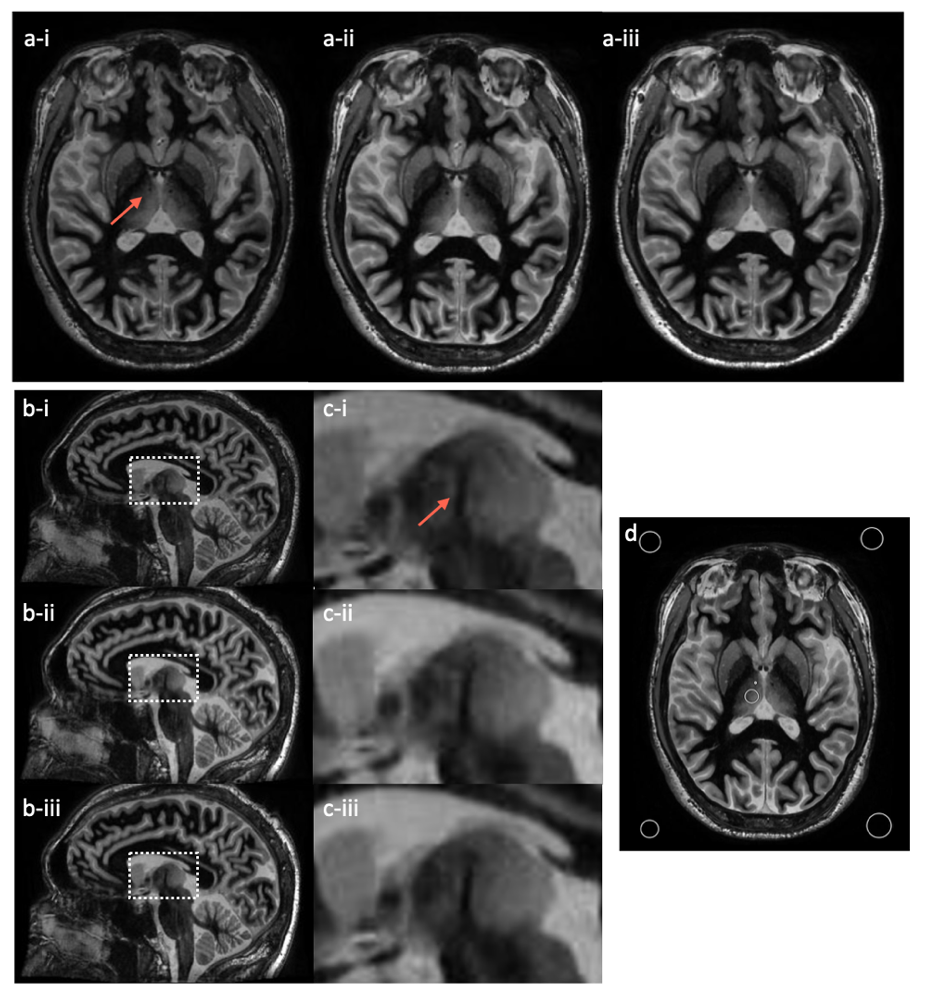

Fig. 3: volunteer images on C3T with magnified inserts. Both the axial plane (a) and the reformatted sagittal plane (b) and (c) are shown for the three protocols (i: 450 ms TI, 8° FA, and ±31.25 kHz; ii: 470 ms TI, 12° FA, and ±31.25 kHz; iii: 470 ms TI, 12° FA, and ±25 kHz). The window/level of all images are set the same. The MTT is marked with an arrow for identification. ROIs are shown in the axial plane for the contrast calculation (d).

Healthy subject scanning: To validate phantom results, a healthy volunteer subject was scanned on the C3T MRI system with high performance gradient [4] under an IRB-approved protocol after obtaining written consent. Our original and modified FGATIR protocols were acquired (Table 1). The imaging protocols for both phantom and subject scans are shown in Table 2. The BW was reduced from ±31.25 to ±25 kHz to extend the TR time on the C3T (6.912 ms to 8.12 ms) to match with the TR time (8.256 ms) on the conventional 3T scanner (GE750) with ±31.25 kHz bandwidth, which demonstrates the benefit of the C3T’s high-performance gradients for reducing TR. ROIs were drawn to calculate the MTT-thalamus CNR (Fig. 3).

Both simulation and phantom experiment demonstrated that the combination of 470ms TI, 12° FA, and ±31.25 kHz BW provided a better MTT-thalamus contrast than the commonly-used protocol of 450 ms TI, 8° FA, and ±31.25 kHz (Table 2). Subject scans on the C3T validated the phantom results (Fig. 3). The demonstration of both ±31.25 and ±25kHz bandwidth shows the high-performance gradients can either be used to shorten TR or lower bandwidth for CNR maximization (Fig. 3).